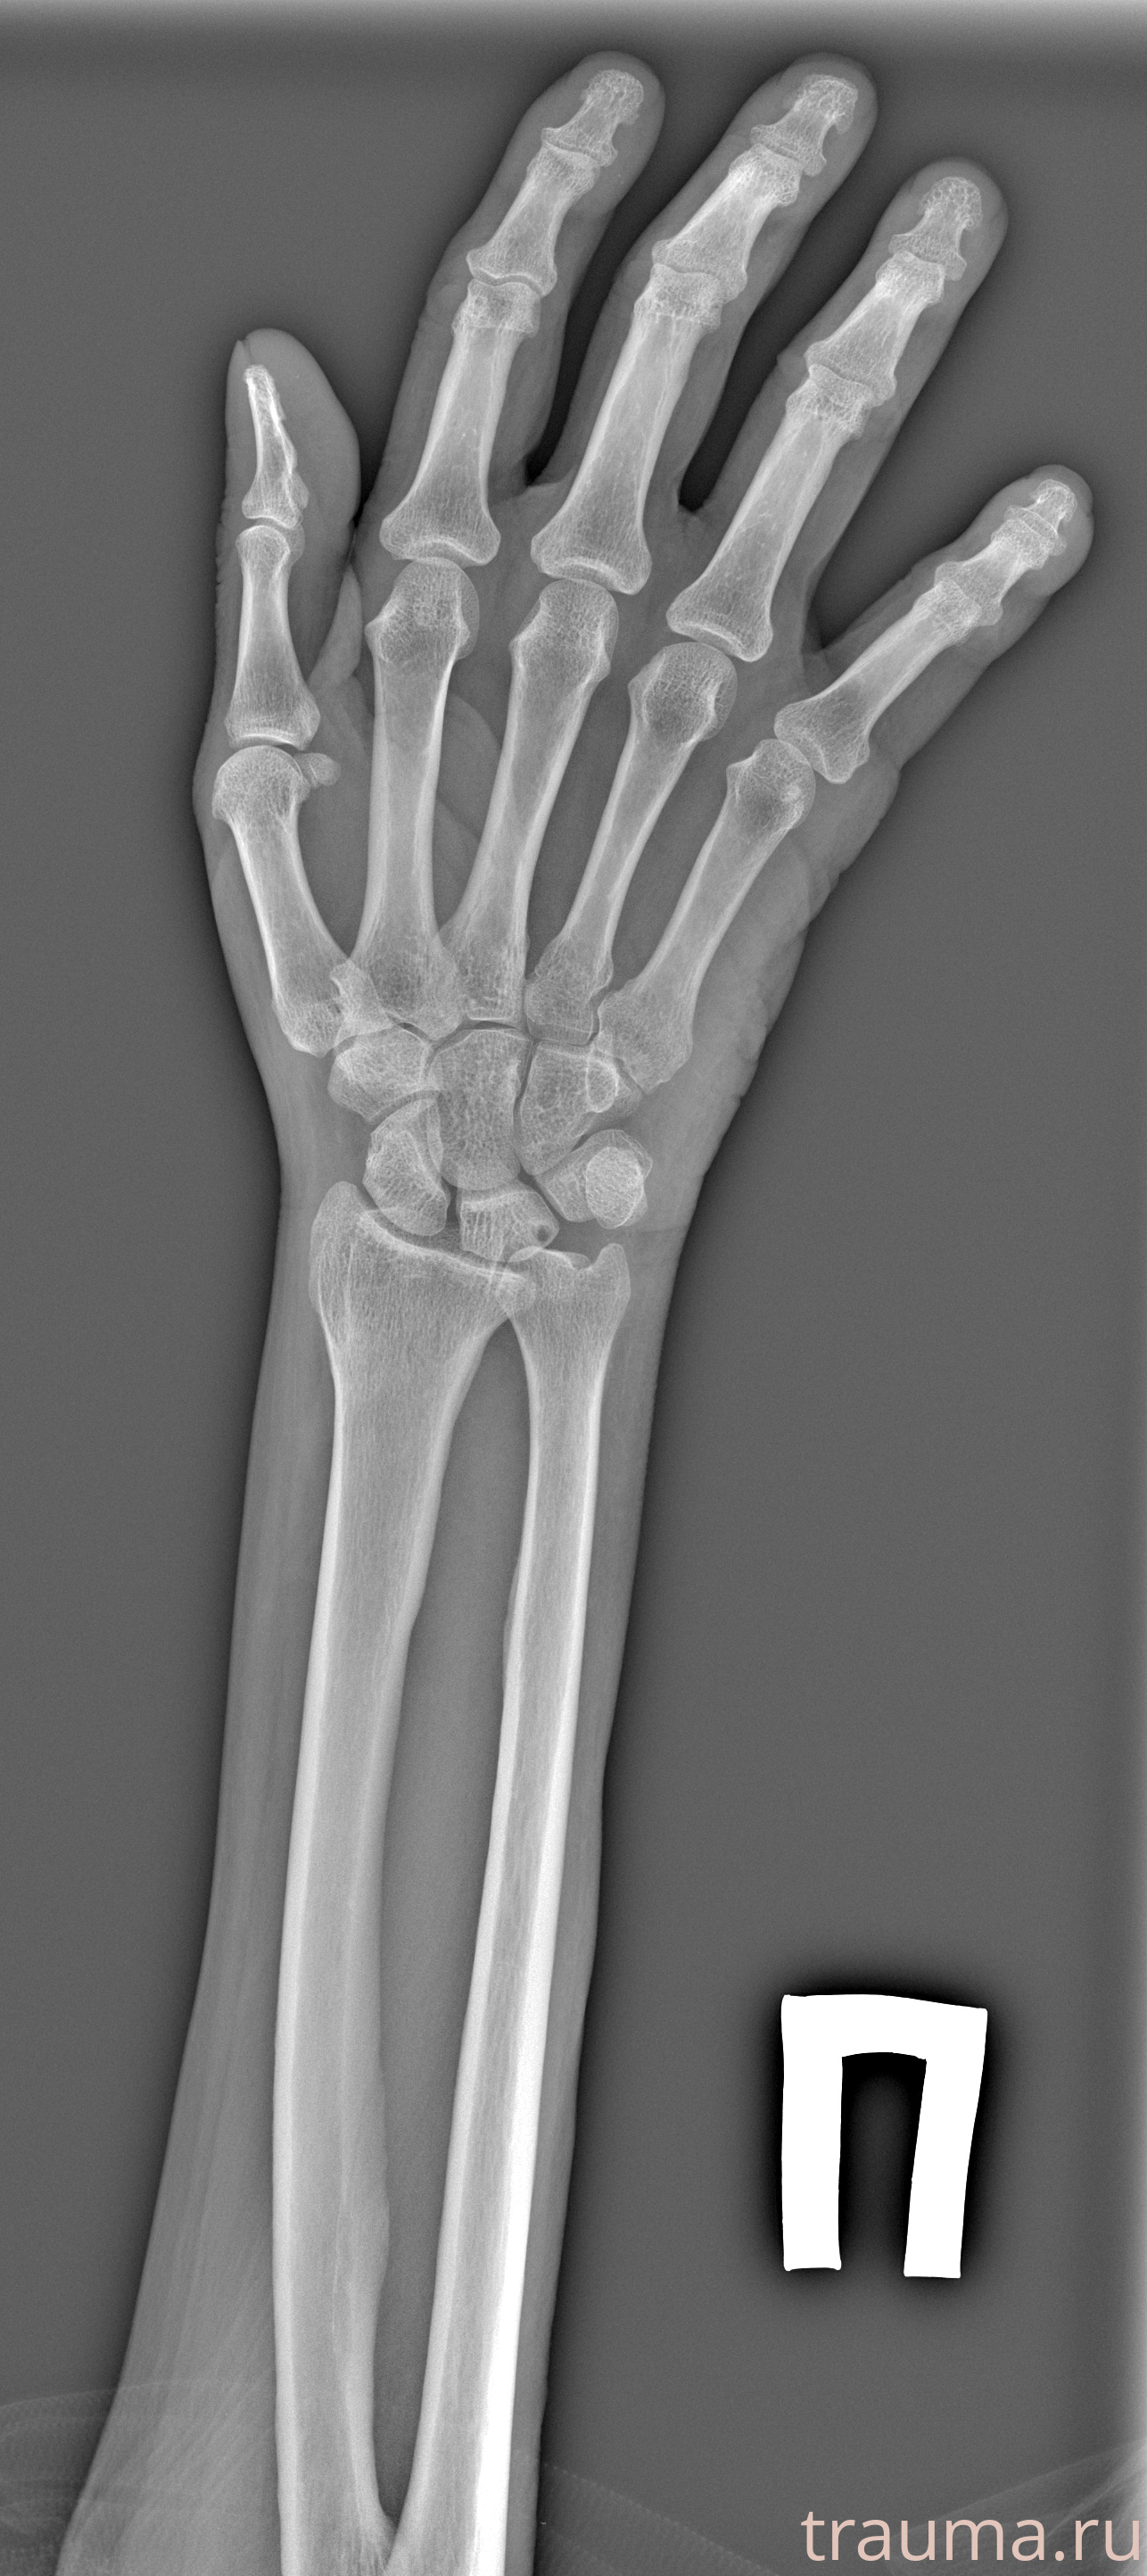

Рентген на дому: по вашему адресу приезжает врач-рентгенолог, травматолог-ортопед с мобильным рентгеновским аппаратом, проводит диагностику травмы или заболевания, делает необходимые рентгенограммы, дает рекомендации по дальнейшему лечению. Получить качественные снимки в домашних условиях возможно благодаря уникальной методике, разработанной МосРентген Центром для института  Склифосовского